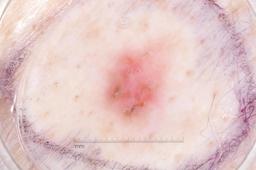

MSK-4

- Name: MSK-4

Description:

Images found based on a search for patients with a personal history, clinical diagnosis, or differential diagnosis of melanoma. All diagnoses confirmed by histopathology.